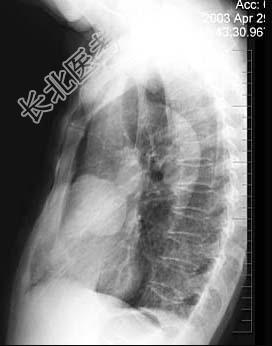

- 单项选择题女性,57岁, 因胸痛,咳嗽1个月就诊, 不发热,咳白色痰, 无痰中带血,X线检查见图, 最可能的诊断是 ( )

D、右肺肿瘤